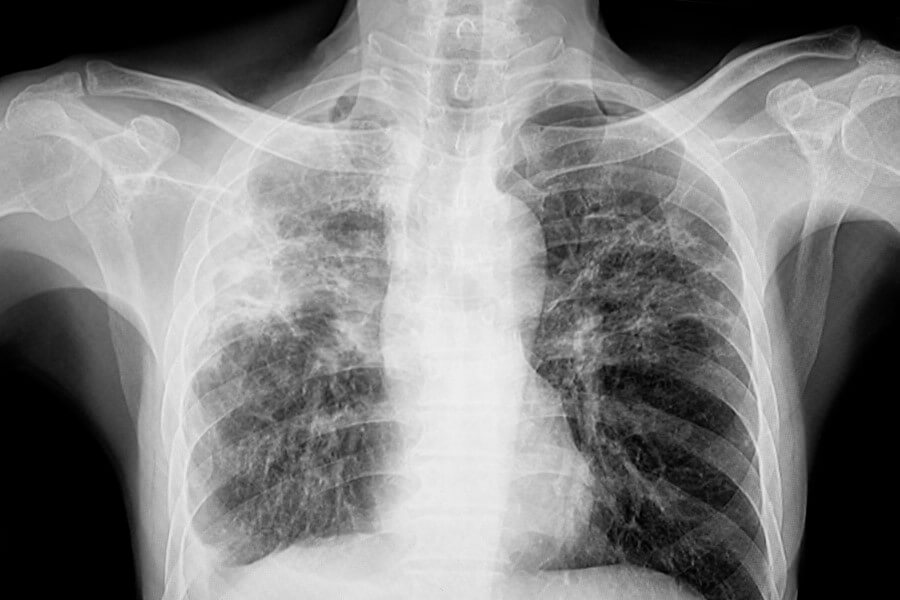

Diagnostyka zwłóknienia płuc wymaga kilku uzupełniających się badań. Podstawą jest dokładny wywiad lekarski, w którym zawarte są pytania dotyczące objawów, ekspozycji zawodowej, chorobach autoimmunologicznych oraz przyjmowanych lekach. Następnie lekarz wykonuje badanie fizykalne, gdzie charakterystycznym objawem mogą być tzw. trzeszczenia nad dolnymi partiami płuc. Kluczowym badaniem obrazowym jest wysokorozdzielacza tomografia komputerowa klatki piersiowej (HRCT), która pozwala zobaczyć typowe dla zwłóknienia zmiany. Ważna jest też spirometria, która najczęściej wykazuje zmniejszoną objętość płuc i pojemność całkowitą. Dodatkowo bada się gazometrię krwi tętniczej, by ocenić poziom tlenu i dwutlenku węgla. W diagnostyczne przydatne są także badania serologiczne, żeby wykluczyć choroby autoimmunologiczne.